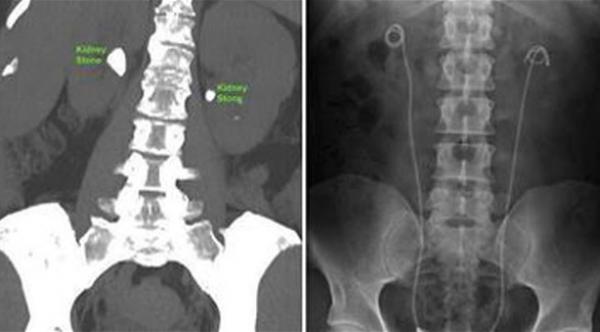

هذه التقنية الجديدة التي تُعرف باسم "bilateral simultaneous ureteroscopy"، تبدأ عبر تصوير وتحديد مواقع الحصوات داخل كلا الكليتين بواسطة منظار الكلى، ثم يُستخدم أشعة الليزر لتفتيتها خلال عملية واحدة فقط بدلاً من اثنين كما هو متبع حالياً.

وطبق استشاري المسالك البولية في مستشفى ساوثمبتون العام البريطانية الدكتور باسكار سوماني، هذه التقنية المستحدثة على 22 مريضاً يعانون من الحصوات داخل كلا الكليتين، وكانت النتائج مبشرة للغاية بعدما وصلت نسبة النجاح إلى 92%.

واستطاع 75% من المرضى ممن يعانون من أوجاع متوسطة مغادرة المستشفى في نفس يوم العملية، وتعرضوا لآثار جانبية قليلة للغاية عند مقارنتها بالأضرار الناجمة عن الخضوع لعمليات جراحية فى كل كلية على حدة.

وكشف سوماني عن هذه النتائج خلال اجتماع الجمعية البريطانية لجراحى المسالك البولية، معتبراً أن هذه التقنية الجديدة ستوفر المزيد من الوقت وستحد من متاعب المرضى والآلام التي يتعرضون لها.